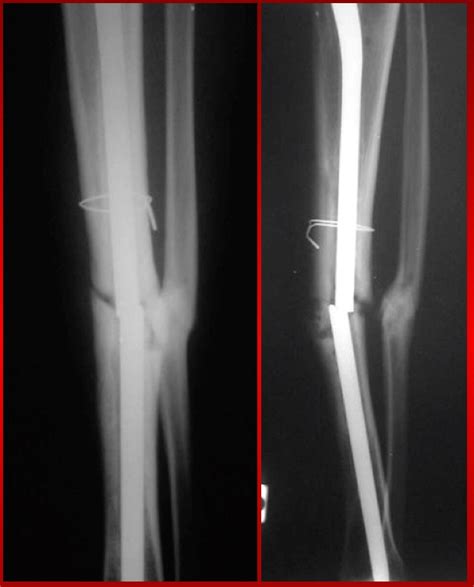

Frattura dell'estremo distale dell'omero - Il Gomito

Frattura dell'estremo distale dell'omero - Il Gomito from www.ilgomito.it